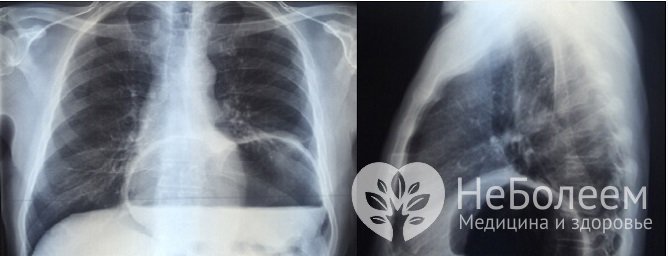

Ущемленная грыжа пищеводного отверстия диафрагмы на рентгенографииЭндоскопическое исследование позволяет выявить достоверные признаки хиатальной грыжи: расширение пищеводного отверстия, смещение пищеводно-желудочной линии вверх и изменения слизистых оболочек пищевода и желудка, характерные для хронического эзофагита и гастрита. Проведение эзофагогастроскопии часто сочетается с рН-метрией; при обнаружении сильных изъязвлений и эрозий также показан отбор биоптата в целях исключения онкопатологии и предраковых состояний.

На рентгеновских снимках хорошо просматриваются признаки аксиальных грыж: высокое расположение пищевода, выпячивание кардии над диафрагмой, исчезновение поддиафрагмального отдела пищевода. При введении контрастного вещества наблюдается задержка взвеси в области грыжи.